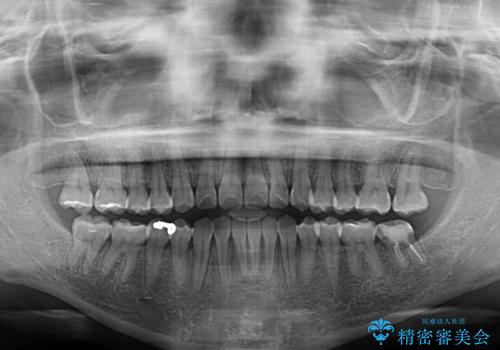

舌の突出癖が認められたため、デコボコ改善に伴い前歯が前突する可能性があったため、舌のトレーニングをしっかりと行うよう指導しながら治療を進めることとしました。

左下の奥歯は根管治療後に放置されていたため、咬み合わせを調整しながら矯正治療を行い、最後にオールセラミッククラウンにて補綴治療を行うこととしました。

舌のトレーニングをしっかりと行っていただき、補綴治療も含めて1年強の短期間で治療を終えることができました。